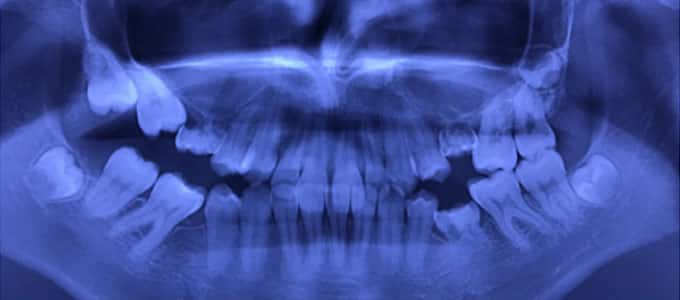

Tratamentul ortodontic nu este o soluție rapidă. Acesta începe întotdeauna cu o examinare minuțioasă a dinților, a buzelor și a întregului aspect facial, sunt necesare radiografii si fotografii de diagnostic. Din aceste informații detaliate medicul ortodont dezvoltă un plan de tratament personalizat.